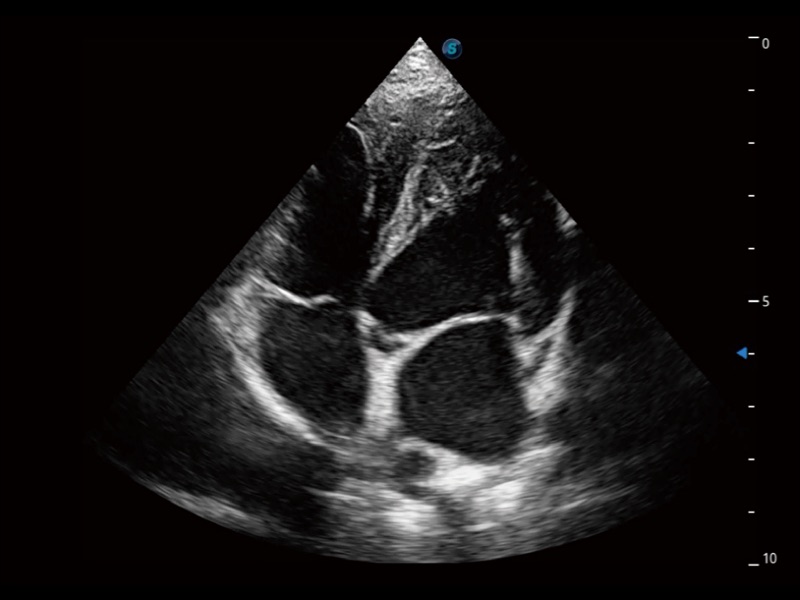

猫、中小型犬及小型异宠动物

ProPet 70 进一步提升了微米成像算法,更加注重对基础原始图像的还原和保留,在有效减少斑点噪声、增强组织边界显示的同时,避免过度优化丟失真实的解剖信息。

ProPet 70专为动物医生设计,对不同的动物体型和生理结构作出了针对性的优化。通过动物影像专用软件,可满足个性化的应用需求,帮助动物医生获得更精确的诊断数据。